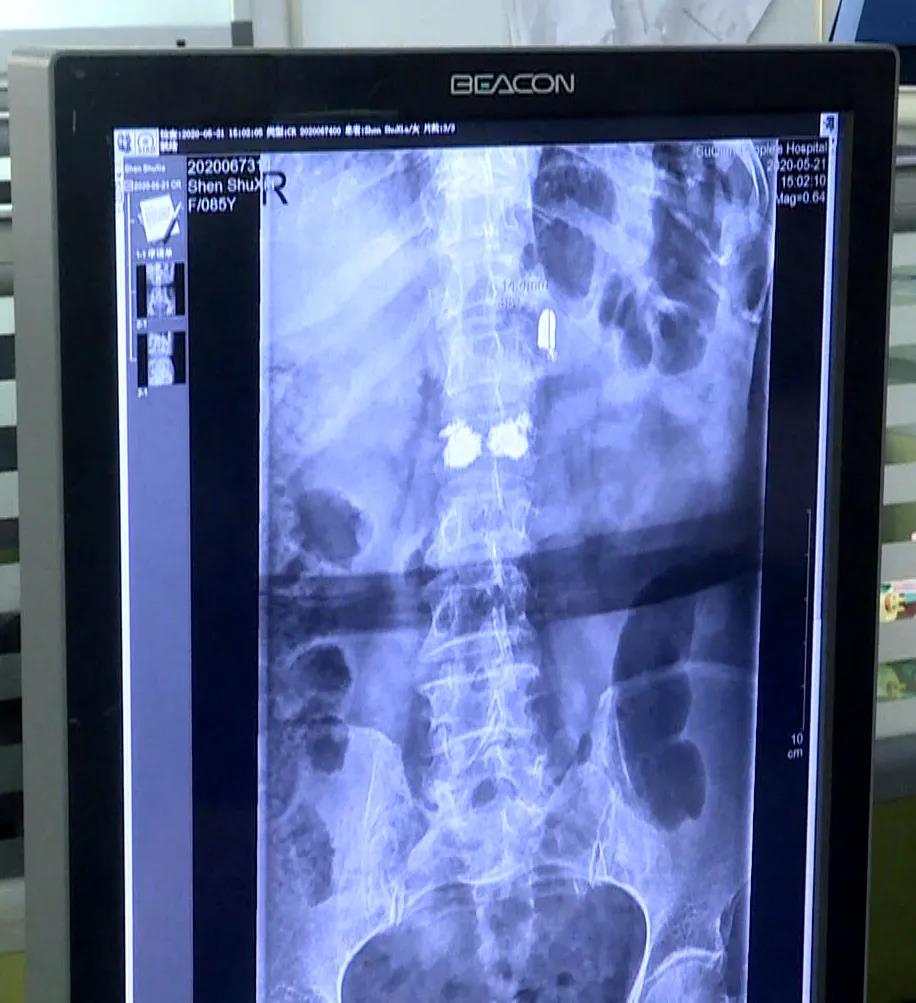

沈书侠昏迷中侥幸存活,事后被亲戚收养,抚育成人。八十年来,失去家人的伤痛和童年的阴影一直伴随着沈书侠老人,但她从没想到自己体内还有一颗子弹。尽管偶尔会感觉到腰部隐隐作痛,但总认为是自己腰不好。由于子弹头潜藏较深,距离老人的腰椎和其他器官较近,加上老人年事已高,手术具有一定风险性,医生不建议将子弹头取出。

沈书侠老人体内这枚80年前的子弹头,是日军侵华残暴对待平民百姓的铁证,它记载着日军对一个五岁儿童的暴行。希望世人能够珍爱和平,勿忘国耻,也祝老人早日康复!